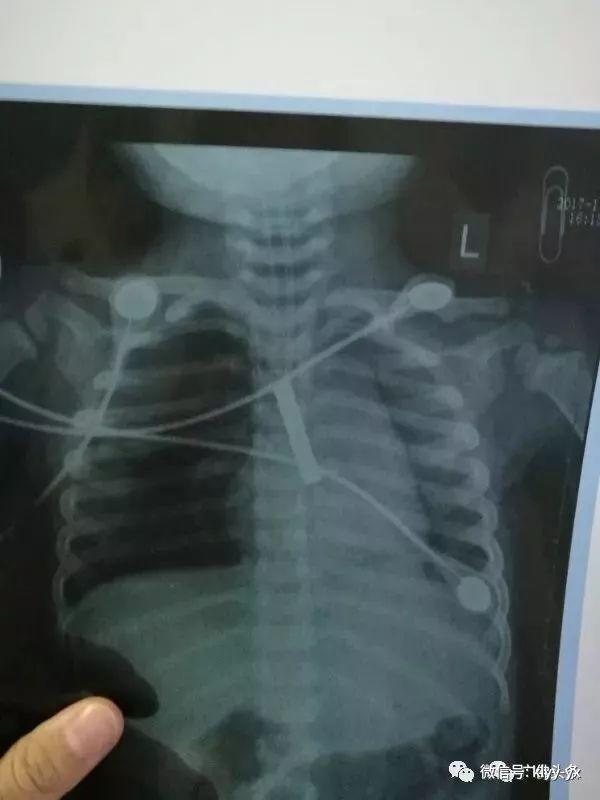

"Kết quả chụp X-quang khiến ai cũng rùng mình. X-quang cho thấy có một vật thể lạ trong khí quản bị tắc nghẽn khiến cho bé không thể thở bình thường và hoạt động trao đổi khí bị ngưng lại" - các bác sĩ cho biết.

Qua phim chụp cho thấy có vật thể lạ bị kẹt trong đường thở của bé.